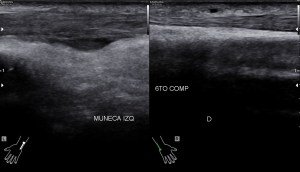

Lo que ves en estas imágenes que te voy a poner aquí son los hallazgos ecográficosque he podido visualizar hoy. Los voy a complementar con la correlación con las imágenes de TAC. En este caso específico con la eco solo se pudo corroborar los hallazgos del escáner, que a nivel anatómico arroja un mejor desarrollo de la anatomía regional implicada en el proceso.

6En el corte longitudinal de la imagen 1 ya se ve una vaso perimetrado por una imagen hiperecogénica, no compresible a la presión con la sonda convexa. En la imagen 2 con la sonda lineal se observa el enrejado habitual de los stents, que en otras ocasiones ya hemos comentado en otro post en localización distinta.